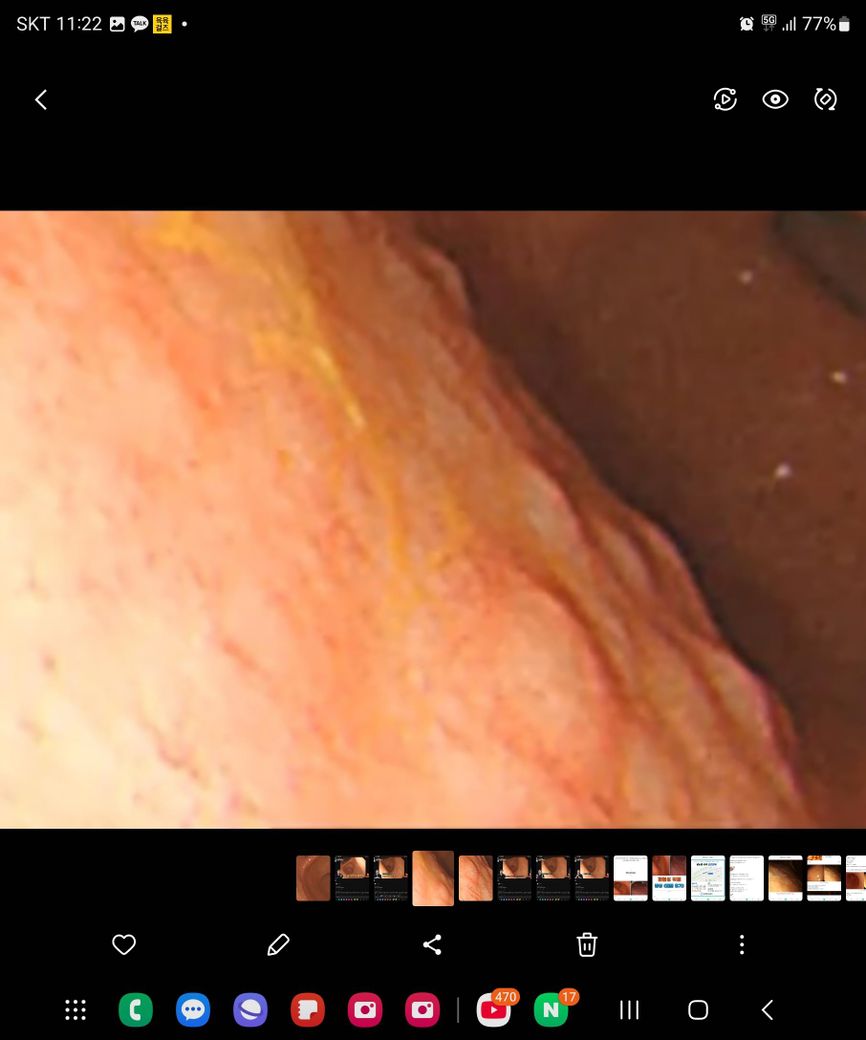

2022년11월달 검진은 이상없었고 이번 검진에서 위내시경에서 오돌도돌한부분 조직을 뗐다는데 신경이 쓰여

오늘 아침에 병원에 한번더 물어보니 내시경한것을 한번더 보면서 설명해주시는데

위가 약한 편이고 사진을 봐서는 괜찮은거 같은데 조직검사 일주일 걸린다고 합니다

올려주신 사진으로 미루어 헬리코박터균과 만성 위염 소견의 가능성이 생각되나 정확하게는 조직검사 결과를 들으시고 만일 헬리코박터균이 동반되어 있다면 건강을 위해 제균치료를 받을 것을 권합니다.

우선은 조직 검사 결과를 기다려 보는 것이 가장 중요하겠습니다. 악성 종양을 강력하게 의심해 보아야 하는 심각한 소견이라고 보기에는 다소 내시경 소견이 비 특이적인 것은 맞습니다. 별다른 문제가 아닐 가능성이 높아 보이긴 하지만 결국에 확실하게 판단을 내리는 데에 있어서는 조직 검사 결과가 필요하겠습니다. 너무 걱정하지는 마시고 일주일 뒤에 검사 결과를 확인하시길 바랍니다.